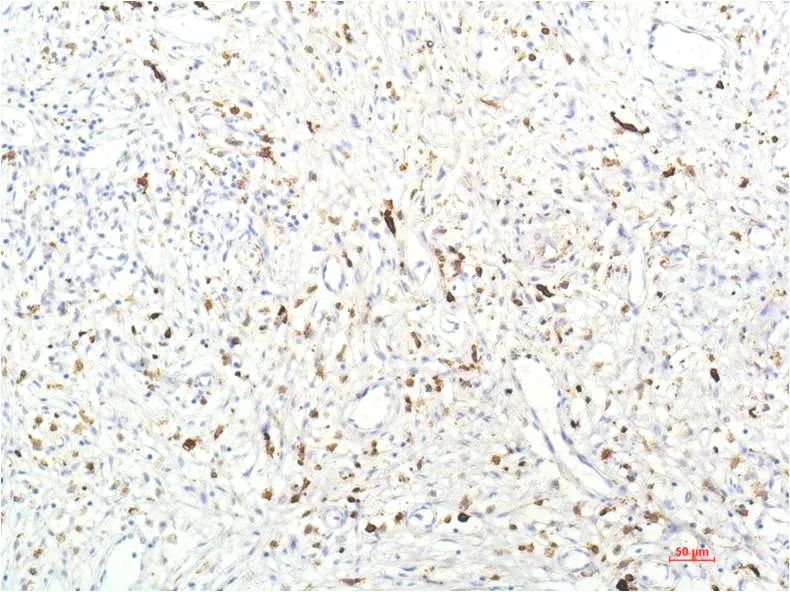

IKB beta (5H3) Mouse Monoclonal Antibody

Cat: AMM00735

Application:IHC-P

Reactivity:Human,Rat,Mouse

Conjugate:Unconjugated

Gene Name:NFKBIB